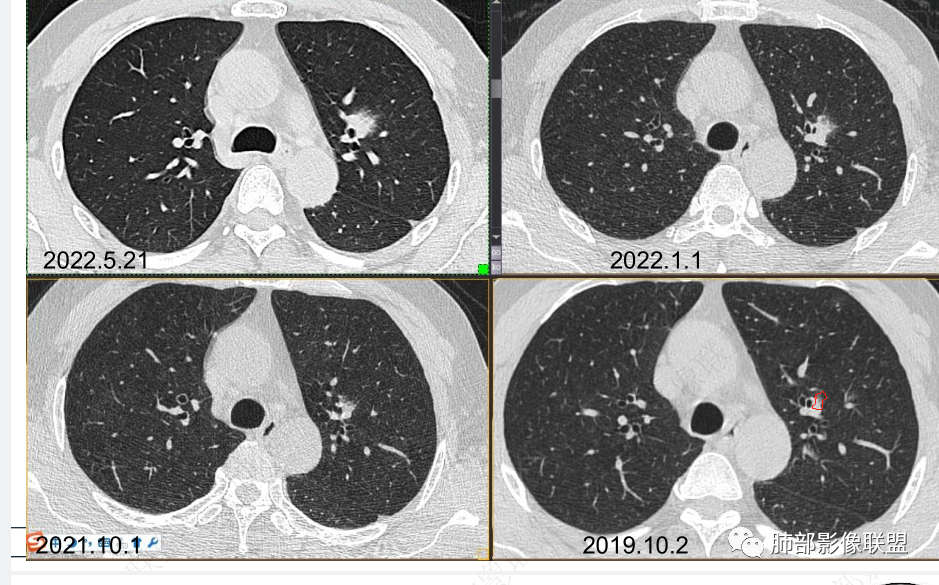

男性,肺结节3年,发现逐渐增大,影像表现,左肺舌段结节,边缘可见磨玻璃密度影,内部走形下舌段支气管变窄,增强呈持续强化,首先考虑肺腺癌,鉴别炎性肉芽肿,真菌/隐球菌。

中老年男性,发现结节,影像表现,左肺上叶结节,实性部分有膨胀性生长,边缘可见磨玻璃影,似清晰似不清晰,病灶与支气管关系密切,部分支气管似狭窄及僵硬,增强病灶强化明显,考虑腺癌(粘液性腺癌)鉴别炎性肉芽肿。

中老年男性,左肺上叶中轴区实性结节及周围磨玻璃影,磨玻璃边界似清非清,关键点2019.10-2021.10-2022.05结节持续增大,增强后明显强化。考虑恶性结节可能大,腺癌(黏液腺癌)?鉴别炎性结节。

361度:

2、病灶以实性密度为主,前、外侧蔓延,GGO部分边界清楚,部分欠清

支气管未见受明显侵犯,未见阻塞,壁增厚,狭窄或扩张。

软组织+重建;病灶实性部分不是类圆形,密度相对均匀柔和。